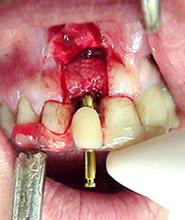

Figura n°4. Esta fotografia mostra a incisão inicial, intra-sulcular, com lâmina N15, para melhor aproveitamento do tecido mole na reconstrução da gengiva marginal do implante. O retalho deve sempre ser total, ou seja, muco-perióstico.

Figura n° 5. Após a remoção de todo tecido de granulação, o guia cirúrgico com o similar do dente a ser colocado foi posto em posição para verificar se estava correto. Pode-se ver que a coroa está em ótima posição em relação à raiz residual que irá ser extraída para colocação do implante.

Figura n° 6. Nesta imagem vemos por palatino o guia cirúrgico em posição. Pode-se ver o topo da raiz e a sombra da linha de fratura já descrita, mostrando que o guia tem sua perfuração para a broca na posição correta.

Figura n°7. Esta fotografia está mostrando a última broca usada (3,15mm) passando pela abertura do guia cirúrgico, antes da aplicação da broca especial do sistema Conect, para

implante de Ø4,3 X 10,0mm. É importante que a última broca de abertura fique na posição o mais ideal possível, pois a posição final, praticamente não pode ser alterada pela última broca do Sistema Conect.

Figura n°8. A fotografia não esta permitindo ver os detalhes, mas a cavidade final está pronta, para receber o implante Conect de Ø4,3 X 10,0mm

Figura n°9. Este é o implante Conect colocado, acreditamos que ele tenha ficado em uma posição ideal. O montador do implante serviu de posicionador para o similar ser vazado em gesso. Isto é, usou-se o guia cirúrgico para fixar o montador do implante, que foi levado ao modelo de estudo e fixado o similar.